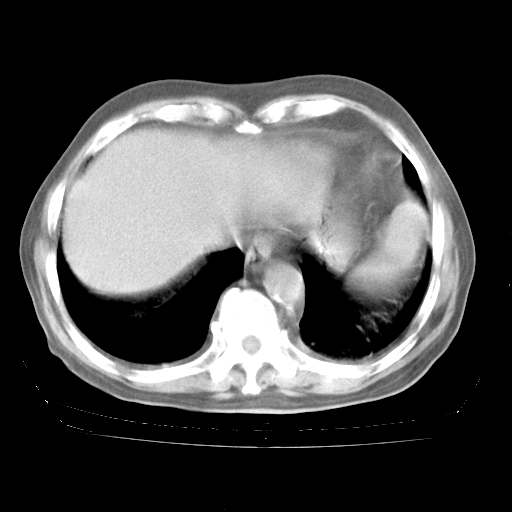

4月28日肺部CT——再次出现类似去年5月9日——磨玻璃样、间有“粟粒样”改变。